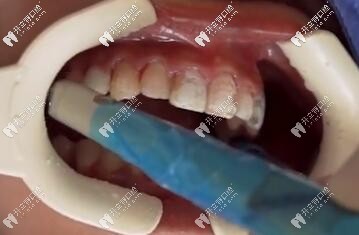

車針卸除貼面

貼面卸除

傳統(tǒng)磨除法

這種方法比較暴力,卸除離不開高速手機(jī)和車針,也是比較常用的方法,時(shí)間長(zhǎng),而且震動(dòng)大。